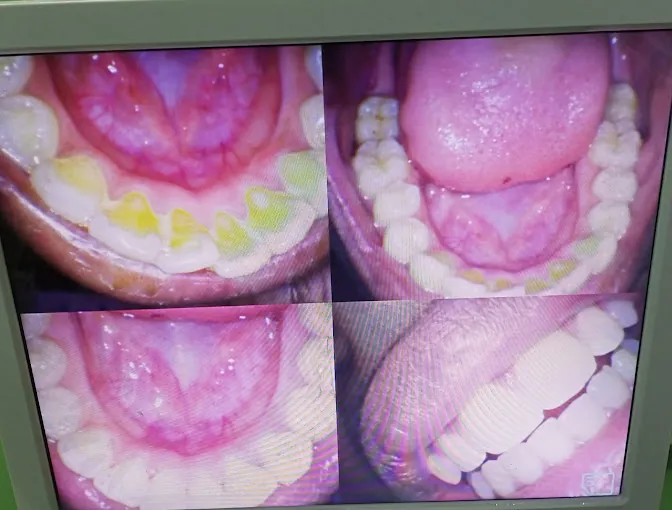

Yahweh Multispeciality Dental Clinic in Kodungaiyur provides top-tier general dentistry, from cleanings to fillings, ensuring your smile stays radiant. Our skilled team uses advanced technology for precise, comfortable care. Open Open daily from 9 am to 9 pm, we’re here at 9384985942. Follow Connect on social media for dental care tips. Let us help you achieve a healthy smile with personalized services.